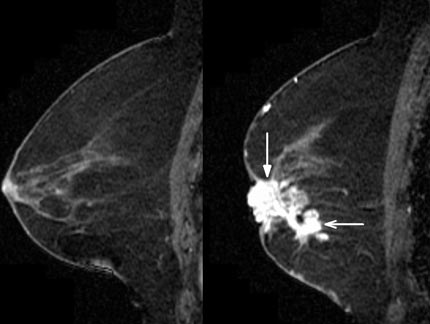

Contraste (un agente basado en gadolinio) es administrado durante una RMN de seno para mostrar áreas sospechosas de ser cáncer lo que demuestra amplificación del contraste (aparece más brillante en comparación al resto del tejido del seno) tal como se ve en la imagen (abajo).

Nota: Las imágenes se muestra para fines ilustrativos. No trate de sacar conclusiones comparando esta imagen con otras en el sitio. Solamente los radiólogos calificados deben interpretar las imágenes.